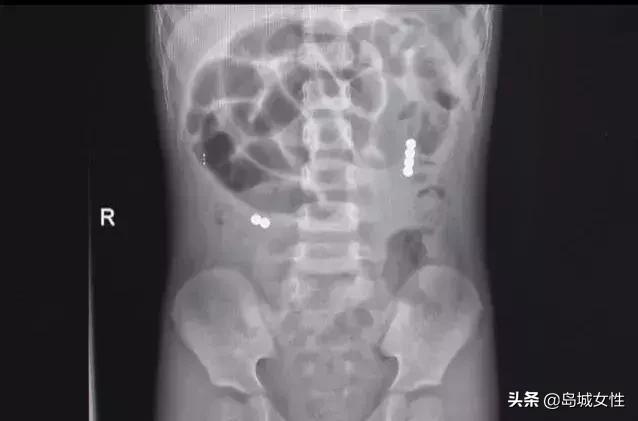

山大齐鲁医院(青岛)

近几年接诊的

消化道异物患儿也不少

来,眼见为实

↓↓↓↓